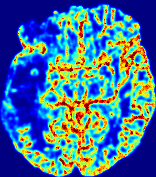

LesionRefer to captionRefer to captionRefer to captionRefer to captionRefer to captionRefer to caption𝐕rgbsubscript𝐕𝑟𝑔𝑏{\bf{V}}_{rgb}Refer to captionRefer to captionRefer to captionRefer to captionRefer to captionRefer to caption𝐕2subscriptnorm𝐕2{\|\bf{V}}\|_{2}Refer to captionRefer to captionRefer to captionRefer to captionRefer to captionRefer to captionRefer to caption3.53.53.52.82.82.82.12.12.11.41.41.40.70.70.70.00.00.0(mm/s)𝑚𝑚𝑠(mm/s)D𝐷DRefer to captionRefer to captionRefer to captionRefer to captionRefer to captionRefer to captionRefer to caption0.0200.0200.0200.0160.0160.0160.0120.0120.0120.0080.0080.0080.0040.0040.0040.0000.0000.000(mm2/s)𝑚superscript𝑚2𝑠(mm^{2}/s)Slice #1Slice #2Slice #3Slice #4Slice #5Slice #6

Figure 4: PIANO feature maps for another patient in the ISLES 2017 training set, where the lesion is located in the right hemisphere. Top row: segmented stroke lesion region (white) on different slices. The corresponding slices for the PIANO feature maps are shown in the following rows.

For a better insight into an estimated velocity field 𝐕𝐕{\bf{V}} and diffusion field 𝐃𝐃{\bf{D}}, we compute the following maps: (1) 𝐕rgbsubscript𝐕𝑟𝑔𝑏{\bf{V}}_{rgb}: Color-coded orientation map of 𝐕=(Vx,Vy,Vz)T𝐕superscriptsuperscript𝑉𝑥superscript𝑉𝑦superscript𝑉𝑧𝑇{\bf{V}}=(V^{x},V^{y},V^{z})^{T}, obtained by normalizing 𝐕𝐕{\bf{V}} to unit length and mapping its 3 components to red, green, blue respectively; (2) 𝐕2subscriptnorm𝐕2\|{\bf{V}}\|_{2}: 222 norm of 𝐕𝐕{\bf{V}}; (3) D𝐷D: scalar field in Eq. 5.

Fig. 3 and Fig. 4 show the PIANO feature maps estimated from two ISLES 2017 patients: all are highly consistent with the lesion in both cases. Details of the blood flow trajectories are revealed in 𝐕rgbsubscript𝐕𝑟𝑔𝑏{\bf{V}}_{rgb} by the ridged patterns and the sharp changes of colors in the unaffected (right) hemisphere, while the flat patterns appearing within the lesion provide little directional information about the velocity and indicate low velocity magnitudes. Velocity magnitudes are more directly visualized via 𝐕2subscriptnorm𝐕2\|{\bf{V}}\|_{2}, from which one can easily locate the lesion where 𝐕2subscriptnorm𝐕2\|{\bf{V}}\|_{2} is low. D𝐷D also indicates lower diffusion values in the lesion, though with less contrast potentially due to the fact that it captures the accumulated effect of CA diffusion at the voxel-level.